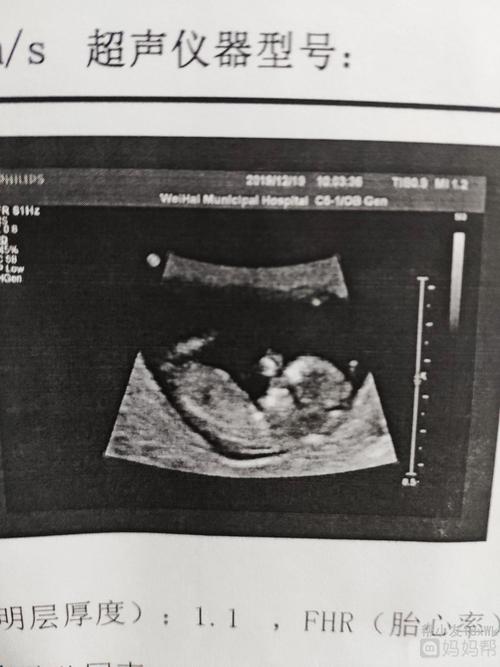

已验证的生女孩nt图

已验证的生女孩nt图,男宝b超图特点男孩

nt通过

nt通过时的照片,两个说男宝的,没有说女

nt照片,能看出男女吗?

nt已过,看看男孩女孩?一胎男孩,这是二